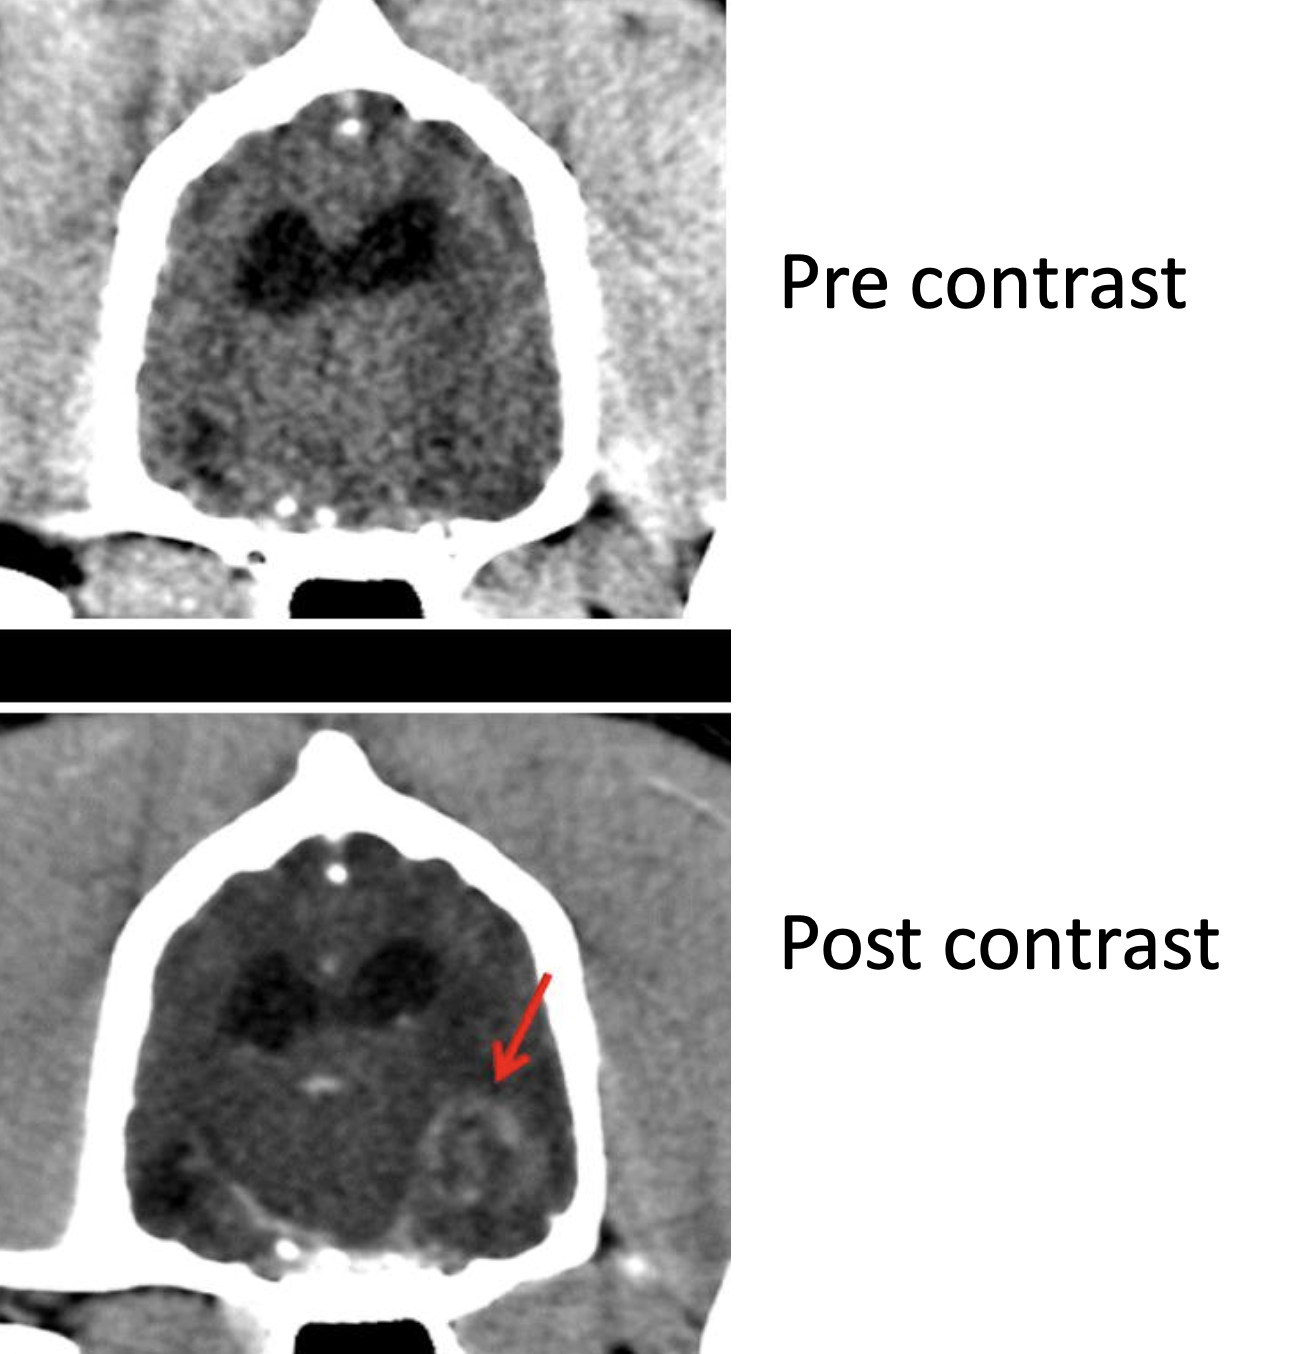

What are the 4 indications for a CT?

Detailed evaluation of bone

fracture repair planning

Image the head

Image spine

Image the abdomen

requires injection of contrast solution to enhance contrast of soft tissues

Any imaging of ______ ______ requires injection of contrast solution to _______

Soft tissue

nhance contrast of soft tissues